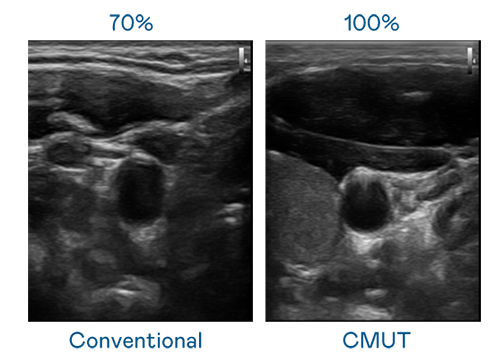

CMUT 技术是一种用电容式微机电元件来产生超音波讯号的技术。与传统 PZT 压电式技术相比,CMUT 频宽增加 30%,更宽频的超音波讯号让影像解析度大幅提升,是实现高影像品质医疗超音波扫描、促进精准医疗发展的关键技术。

超音波影像的解析度高低,首先取决于探头能发出的讯号频宽。伟德国际1946 CMUT 可提供高清晰的超音波讯号,提供高频宽、高灵敏度、影像纹理细节更高的超音波影像,协助医护人员缩短影像判读时间及利用精准的医疗影像进行诊断。